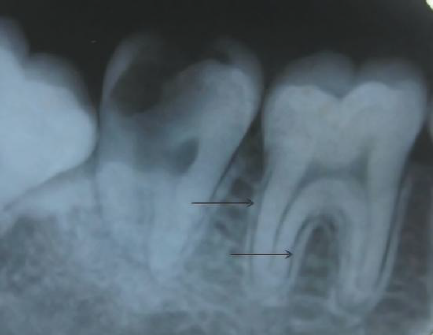

71. What is showing by arrow?

"Lamina Dura" : a thin radiopaque layer of dense bone bounding the tooth socket. It is continuous with the shadow of the cortical bone at the alveolar crest. The presence of an intact lamina dura around the apex of a tooth strongly suggests a vital pulp.